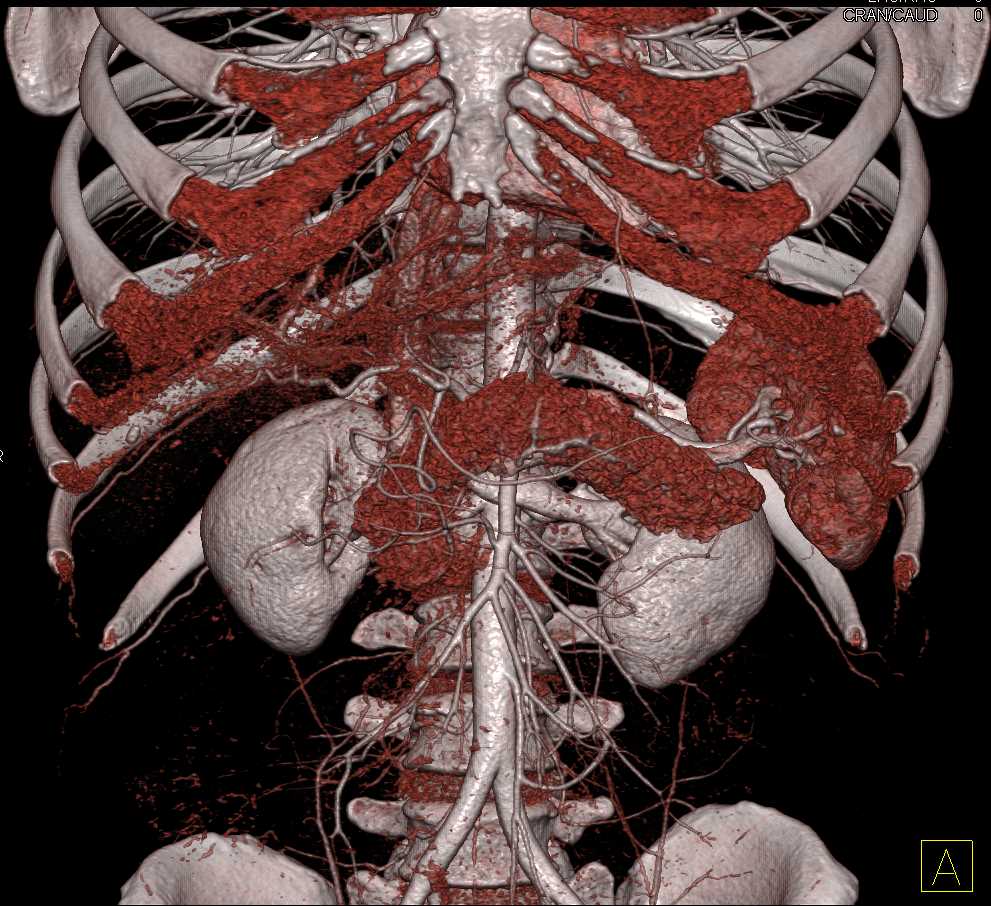

Neuroendocrine Tumor Body of Pancreas